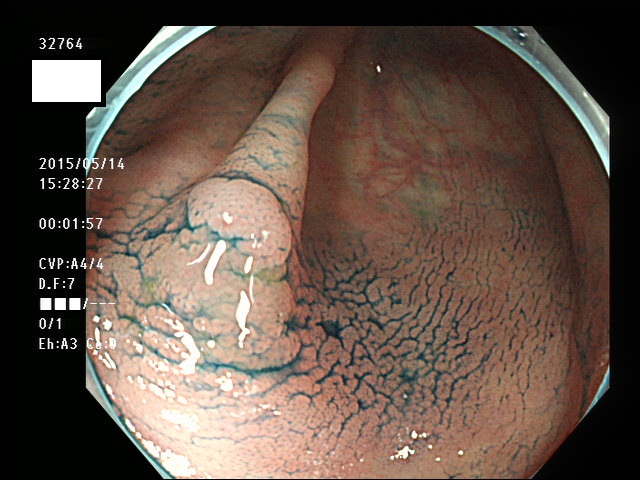

上記100名より抽出した平坦・陥凹型腺腫(=癌化の危険が高いが見落としやすい病変)の内視鏡写真

腺腫発見率 57% (カルテ番号32700〜32799の100名の方の検査結果で集計)

以下のカルテ番号の方に腺腫(Adenoma,Group3〜5)が見つかりました

32749 32750 32751 32753 32757 32759 32760 32761 32763 32764 32765 32766